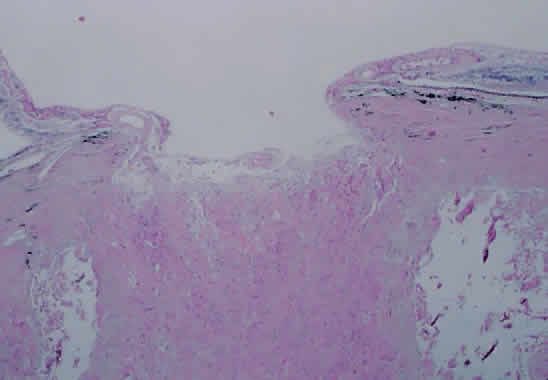

TOXOPLASMOSIS RETINOCHOROIDITIS. Toxoplasmosis accounts for 1% to 5% of AIDS-related retinal infections and usually is acquired as opposed to being congenital.110 Toxoplasmosis in the immunocompromised host differs in its clinical manifestations to that of the immunocompetent host. There tends to be less intraocular inflammation, lack of a preexisting pigmented chorioretinal lesion, and larger, more hemorrhagic areas of involvement, which may be bilateral.110–112 Histopathologic analysis of cases of toxoplasmosis in patients with AIDS shows the presence of Toxoplasma cysts, necrosis of the retina, and a minimal lymphocytic infiltrate within all layers of the retina (Fig. 13).110 In addition, the choroid shows the presence of histiocytes, plasma cells, and eosinophils.113

Fig. 13 A. Right fundus from patient with the acquired immunodeficiency syndrome showing a large area of necrotizing retinitis (pigmentation within area of necrosis, possibly representing previous site of activity) with hemorrhage, which, on histopathologic analysis (B and C), revealed retinal necrosis and the presence of cysts consistent with Toxoplasma gondii (hematoxylin and eosin; B × 200, C × 500). D. Electron microscopy shows tachyzoites within cysts.